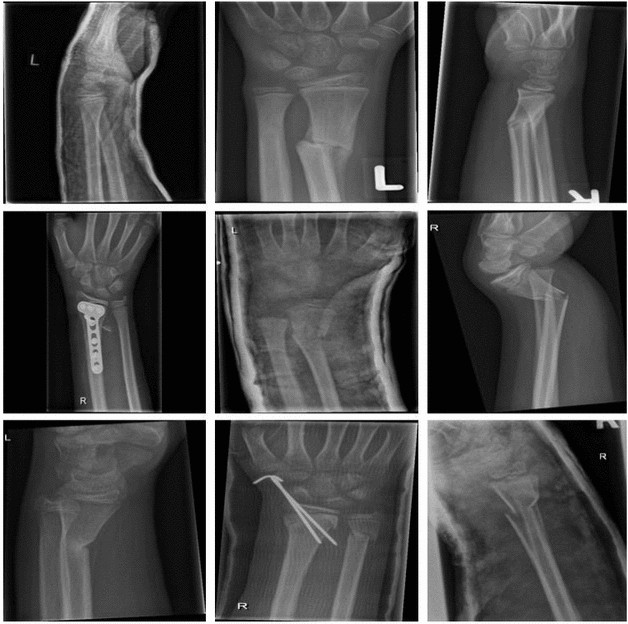

This investigation utilizes the GRAZPEDWRI-DX dataset, a publicly available resource curated and disseminated by Nagy et al.19 with the explicit aim of advancing computer vision research. The dataset comprises a cohort of 6091 pediatric patients (mean age: 10.9 years; range: 0.2–19 years; 2,688 female, 3402 male, one of unknown gender), all of whom were managed at the Department of Pediatric Radiology, Medical University of Graz, Austria. The dataset encompasses a substantial corpus of 20,327 wrist radiographs, including both lateral and posteroanterior projections. These images were acquired between 2008 and 2018, with the annotation process being conducted from 2018 to 2020 by a team of professional radiologists and medical students. Critically, the fidelity of all annotations was subsequently corroborated by a panel of three senior radiologists. Notably, the dataset provides a high data density with an average of approximately 3.34 images per patient. This multiplicity arises from the standard clinical protocol of acquiring multiple projections (e.g., posteroanterior and lateral views) and serial follow-up examinations for individual patients. Such a structure allows the model to learn fracture features across varied projection angles and developmental stages. Exemplar images from the GRAZPEDWRI-DX dataset are presented in Fig. 1.

Sample GRAZPEDWRI-DX dataset.